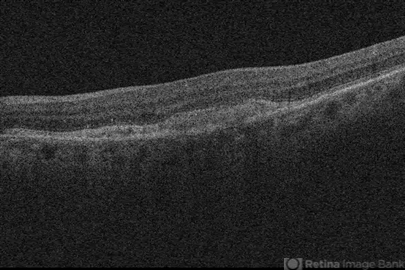

Fairly homogenous material between the RPE and PR. No srf, cme, or leakage on FA

- aquired vitelliform maculopathy

Optical coherence tomography system

Cirrus - Description

- Initial presentation.